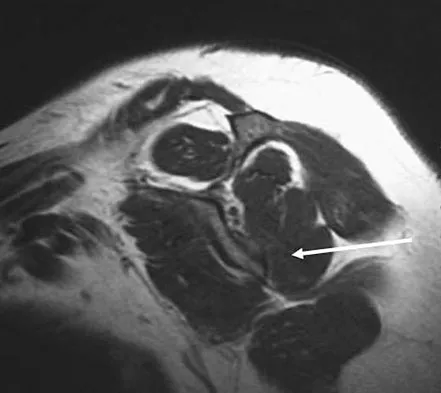

A 19-year-old man has had back pain with activity, especially running in soccer and baseball, for the past 4 months. He denies any history of trauma. Examination reveals no motor weakness or sensory changes in the lower extremities. Range of motion shows increased pain with extension and mild limitation with flexion. A sitting straight leg raising test is limited at approximately 60 degrees bilaterally by back and buttocks pain. Plain radiographs are normal. MRI scans are shown in Figures 13a through 13e. What is the most likely diagnosis?

Explanation